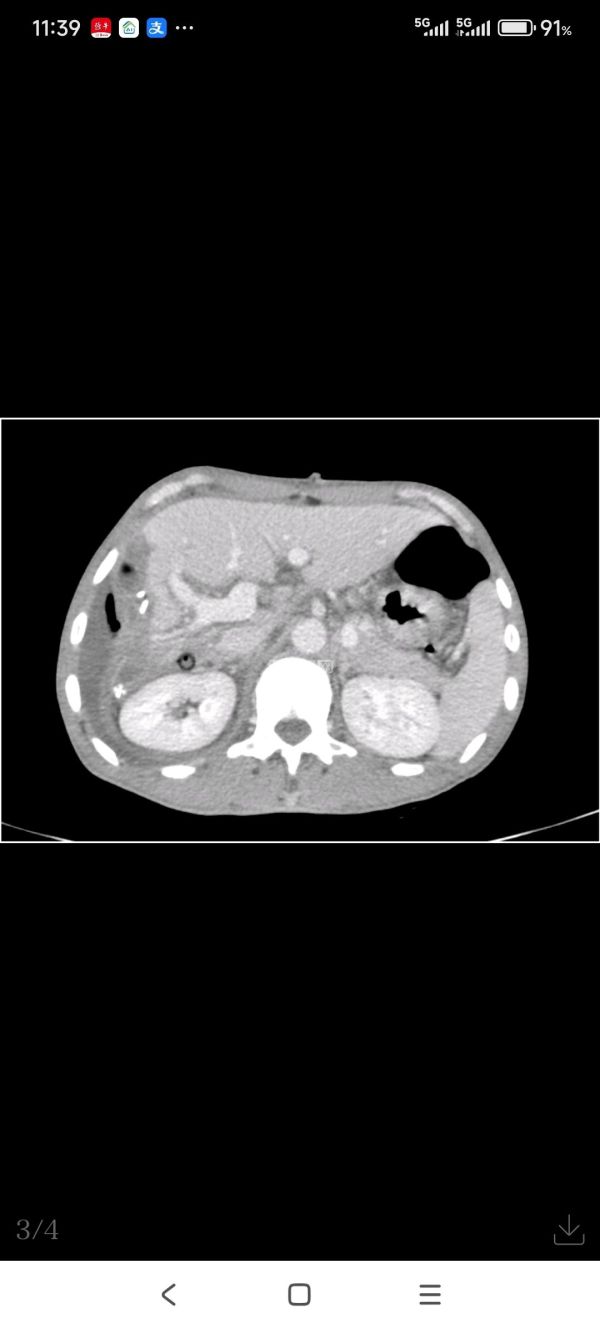

原来,徐先生今年53岁,是家中的顶梁柱,平时身强力壮,但半月前体检时不幸被确诊为肝癌,肿瘤巨大,12×8cm左右,位于右肝,靠近膈顶部,手术难度极大、风险较大,徐先生一家陷入巨大的不安之中。

徐先生的CT和MRI检查结果

肿瘤的大小确实令人倒吸一口冷气

入院后,医生利用智能肝脏分析系统重建了肝脏3D图像,清晰地显示了肝脏巨大肿瘤的立体图像,评估了肝肿瘤与周围血管的关系及剩余肝体积、测量了肝脏的储备功能,并且完善了相关术前检查,确定肝脏肿瘤可安全切除。

无独有偶,72岁的邬先生也被诊断左肝巨块型肝癌,12×10cm左右,也在绍兴市人民医院肝胆胰外科实施了精准肝癌切除术,术后一周顺利出院。